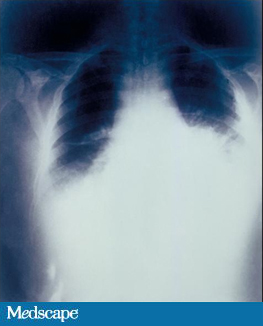

B.anthracis is a spore-forming, gram positive bacillus, which when inhaled carries a high mortality. The spores can enter the body cutaneously, enterally, via injection or via inhalation. Patients with inhalation anthrax will present with fever, chills, headache, chest pain, cough and difficulty breathing, and will require hospitalization even though they may not appear critically ill. These patients are susceptible to sudden decline and hemodynamic monitoring should be initiated. Chest CT and CXR will show characteristically widened mediastinum and pleural effusions.